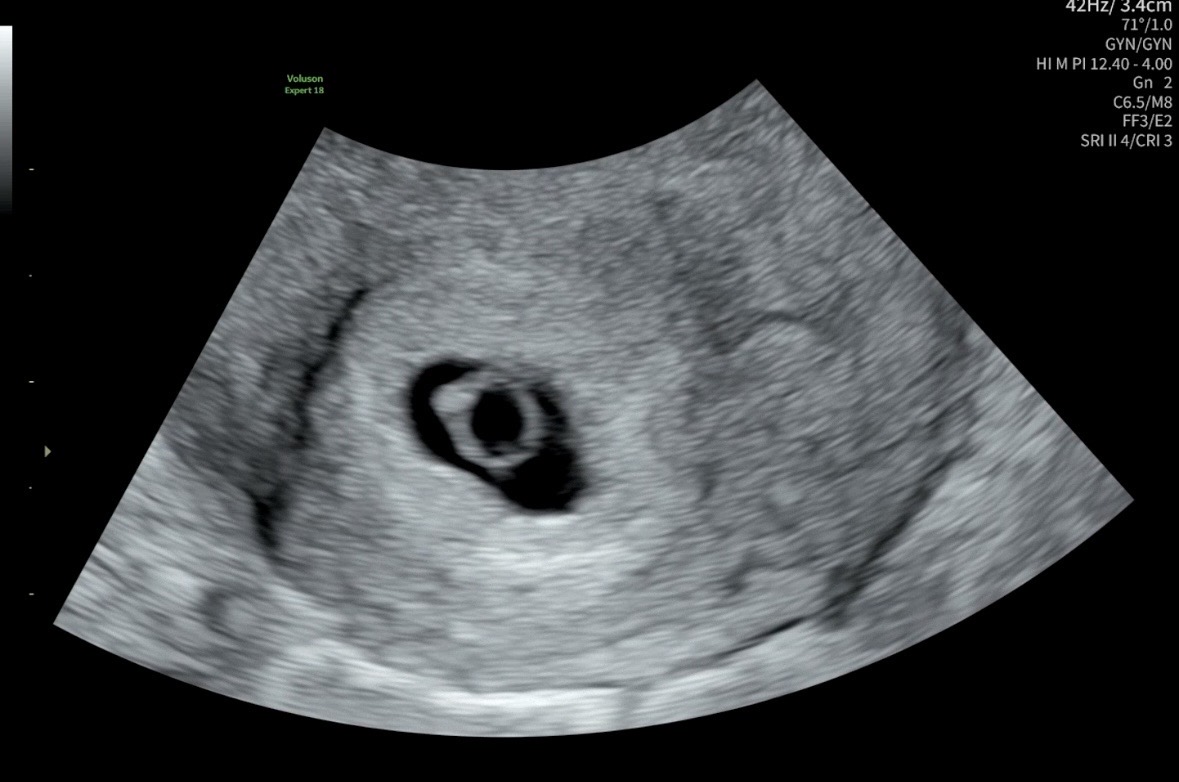

오늘 6주 다이아반지 보고왔어요✨

자궁외 임신 후에 찾아온 소중한 아이 ㅎㅎ 심장소리도 들었는데 엄청 귀여워요 ㅠㅠ